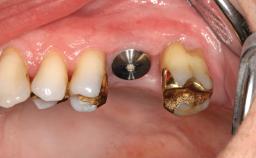

A 61-year-old woman was referred for assessment of the possibility of bone grafts for implant placement to reconstruct her severely atrophic maxilla. She was a healthy non-smoker. Since her thirties she had worn a complete upper denture against a natural lower dentition. Ten years prior to the consultation, five implants had been placed in the maxilla for a fixed prosthesis. One implant failed immediately, and others failed over the ensuing 10 years. In the previous 2 years, she had been wearing a complete denture without retentive elements over the last two implants. Her primary concern was the instability of her denture. She had great difficulty with mastication and felt insecure when speaking. Her desire was to have a fixed prosthesis.